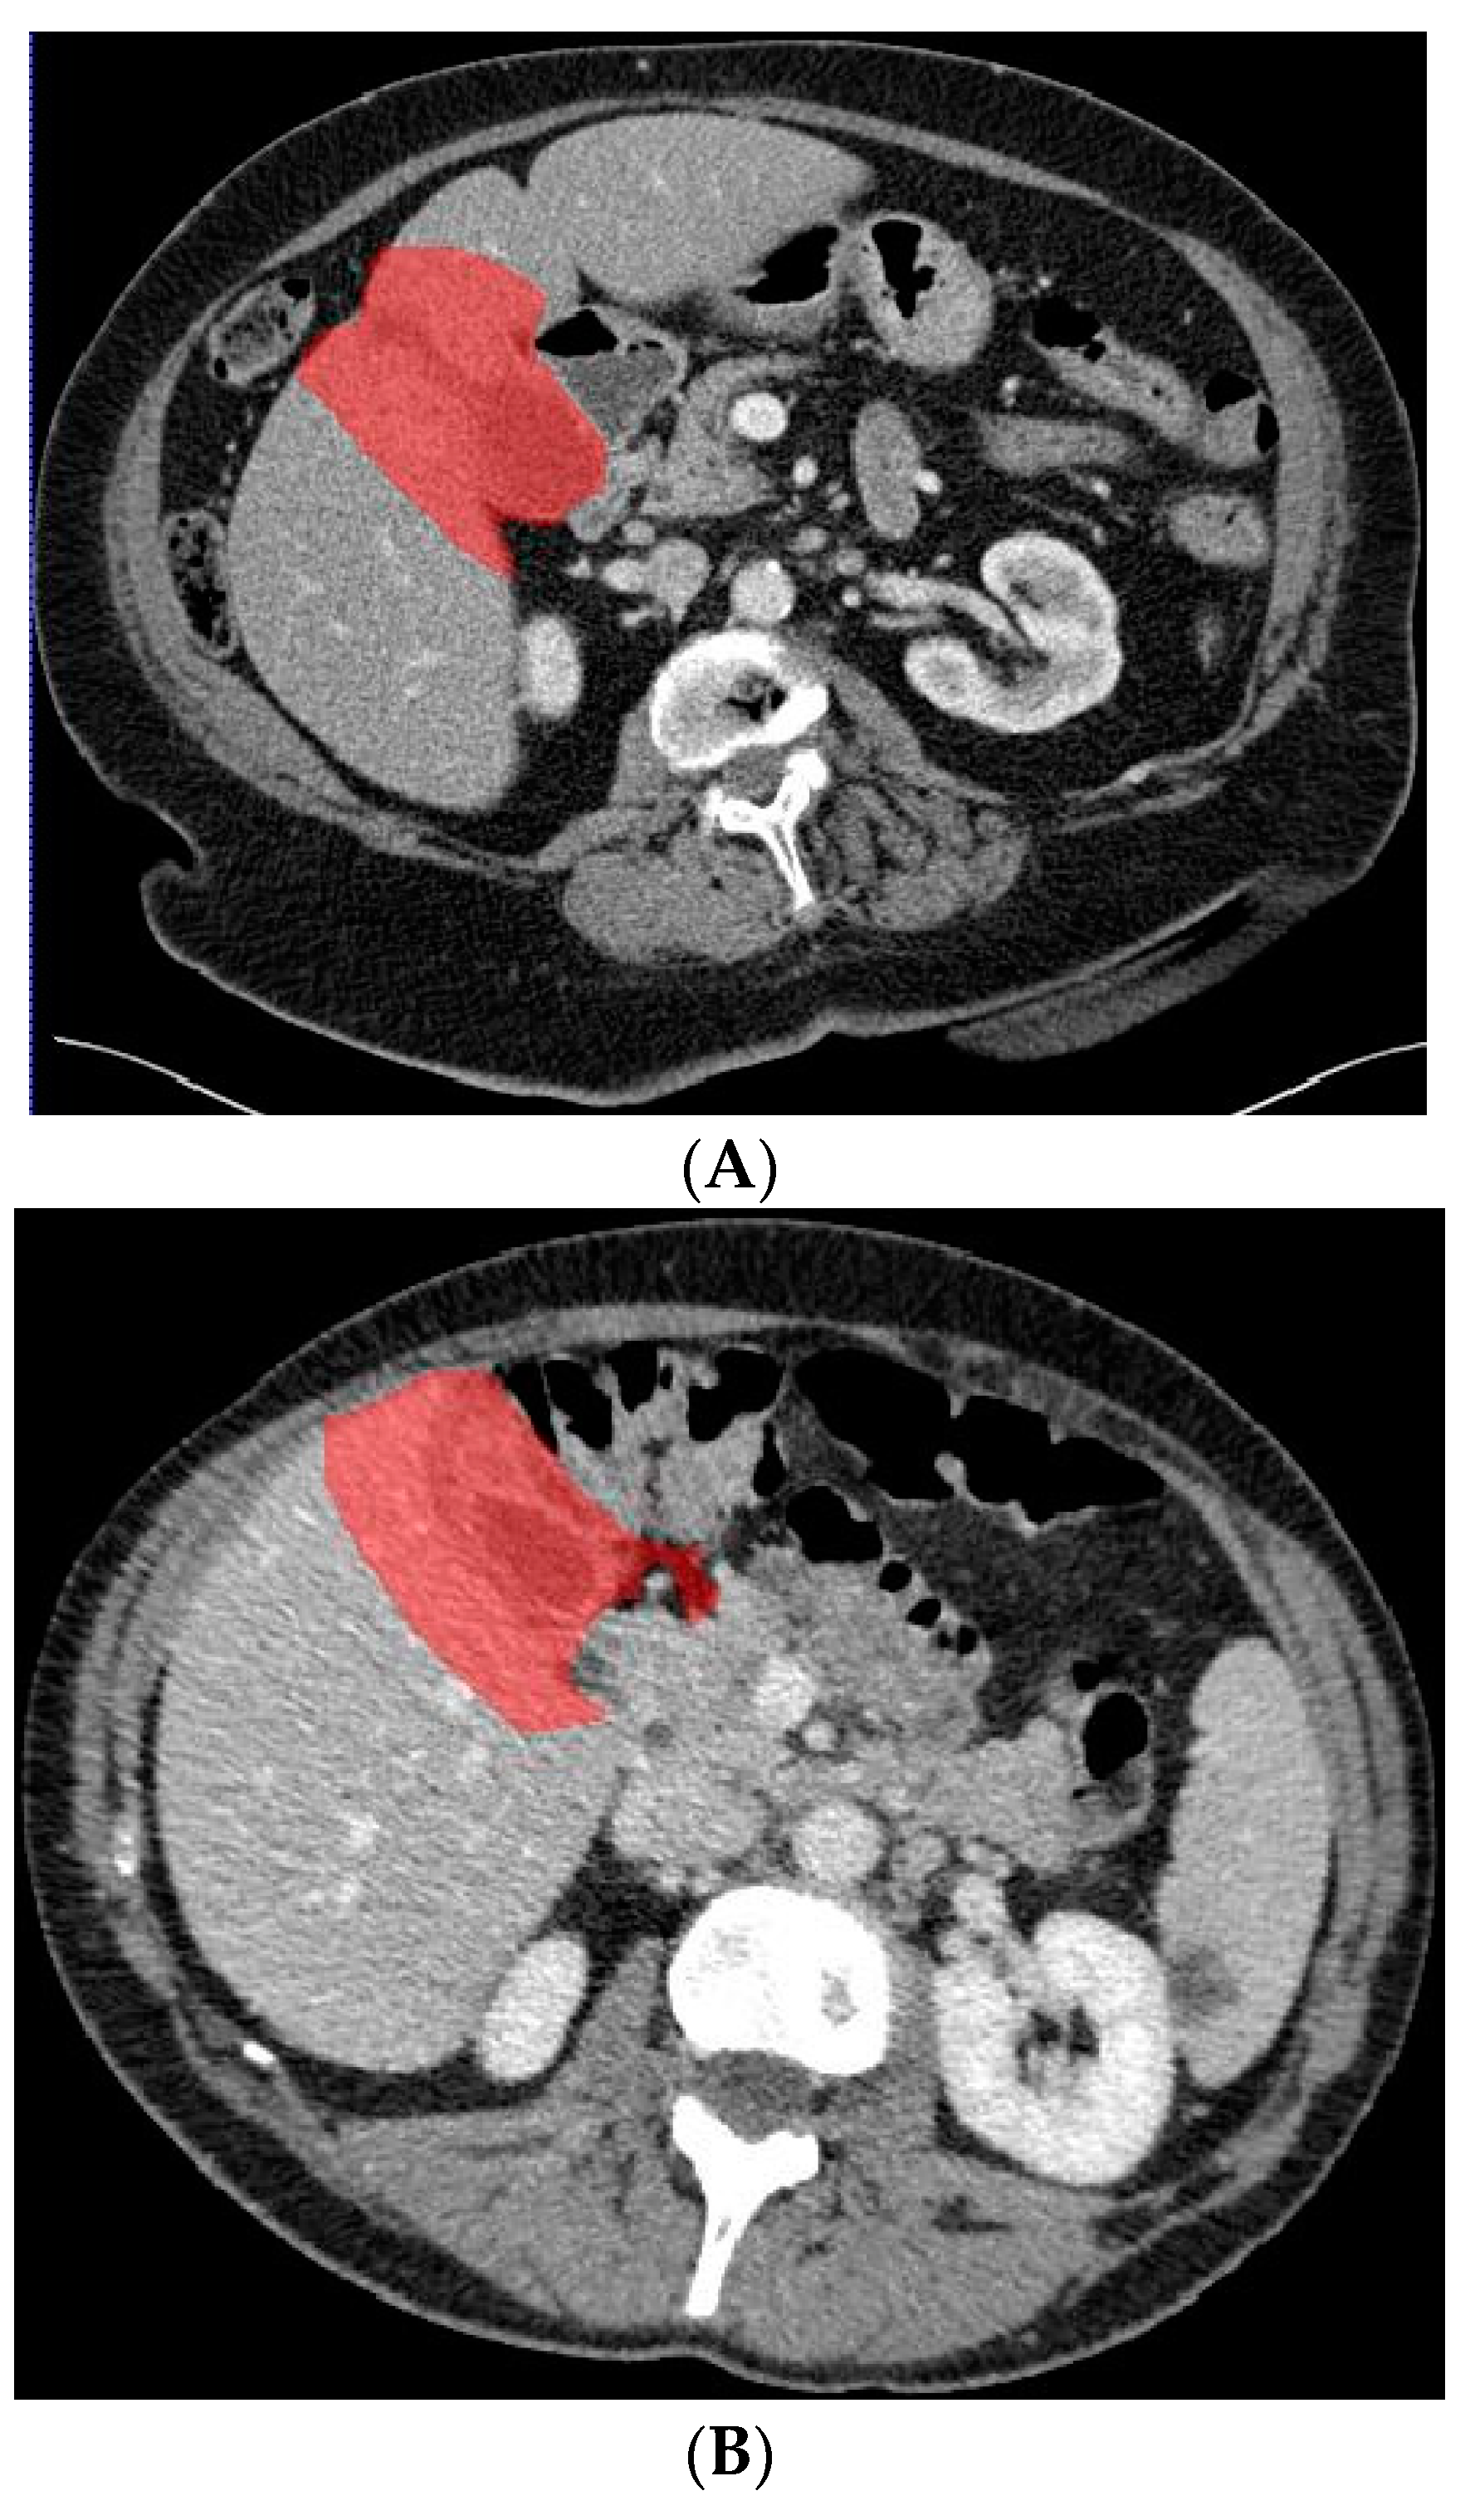

In a previous study, the suspicion of invasion of adjacent liver parenchyma was observed to be positively related to GBC [5]. Therefore, in addition to using only the gallbladder on CT images when training the deep learning model, a separate analysis was performed to investigate whether the combination of the gallbladder and adjacent liver parenchyma could increase the performance of the deep learning model when differentiating between GBC and benign gallbladder disease. The segmentation of a 2 cm rim of liver parenchyma adjacent to the gallbladder was automatically generated and adjusted by an experienced abdominal radiologist if necessary. The adjacent liver parenchyma was combined with the segmented gallbladder as training data for the deep learning model. Figure 4 shows examples of input CT images with segmentation of both the gallbladder and 2 cm of adjacent liver parenchyma. The deep learning model based on the combination of the gallbladder and adjacent liver parenchyma was trained and tested by the same methodology as described for the model solely based on the gallbladder.